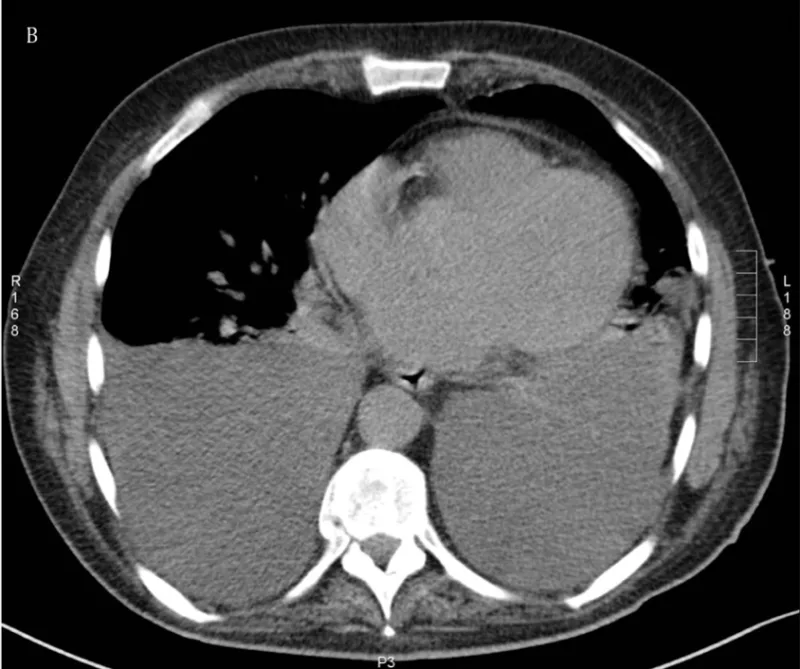

本来は, 空気が入っていて, 黒く写る肺の背中側(画面の下側)に灰色に写る水(胸水)が貯まっており, それによって肺が半分ほどしか写らなくなっています.

胸部CTでは, 両側に大量の胸水が貯まっていました.